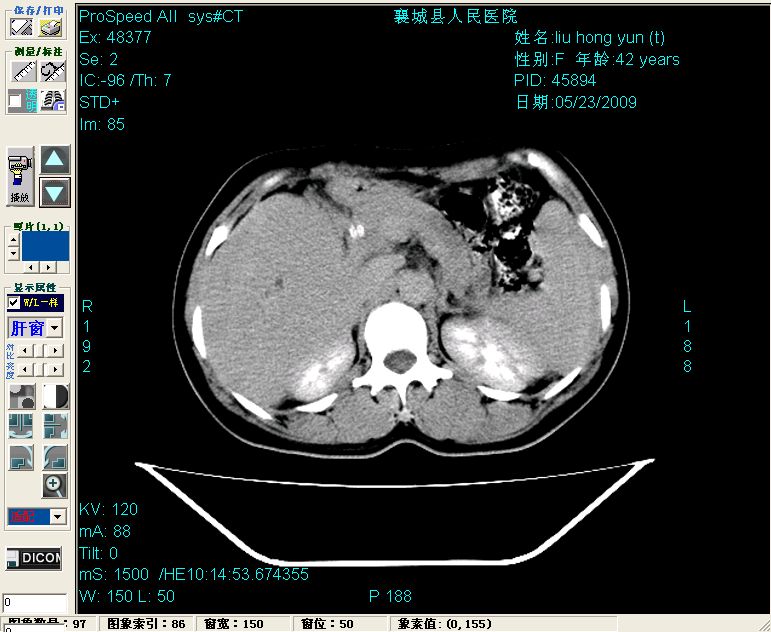

增强:

增强动脉期前述低密度区轻度早其强化,门脉期强化程度显著增高,延期扫描强化程度下降,但仍为相对高密度影

胰头部见结节状高密度影,其前方略可分辨扩强胆部管,平扫到增强始终有,但现在尚难与胃肠造影剂鉴别.

2左肝及右肝前叶表现考虑胆囊摘除术后所致的肝动门脉瘘形成,慢性纤维组织炎性增生.不完全除外左肝胆管细胞癌

3脾大,可能与动门脉瘘所致门脉高压有关